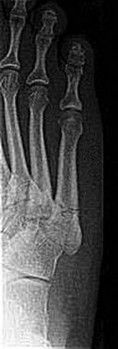

Question 17:

A 25-year-old male injures his midfoot when falling from a horse with his foot caught in the stirrup. Radiographs show a widening of the space between the base of the 1st and 2nd metatarsals. Which ligament is primarily ruptured in a classical Lisfranc injury?

Correct Answer: Ligament connecting the 2nd metatarsal base to the medial cuneiform

Explanation:

The Lisfranc ligament connects the medial cuneiform to the base of the second metatarsal. It is a critical stabilizing structure of the midfoot, and its rupture leads to instability.